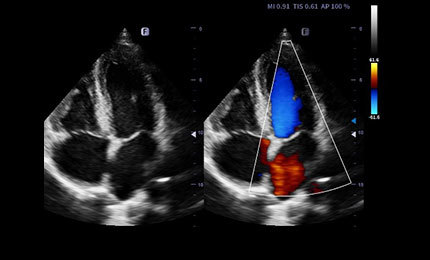

Tissue Doppler Imaging

Tissue Doppler Imaging (TDI) is a robust and reproducible echocardiographic tool that employs the Doppler effect to assess muscle wall characteristics throughout the cardiac cycle including velocity, displacement, deformation, and event timings. It has permitted a quantitative assessment of both global and regional function and timing of myocardial events